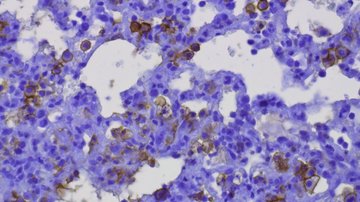

Moudra A, Hubackova S, Machalova V, Vancurova M, Bartek J, Reinis M, Hodny Z, Jonasova A. Dynamic alterations of bone marrow cytokine landscape of myelodysplastic syndromes patients treated with 5-azacytidine. Oncoimmunology. 2016 May 13;5(10):e1183860.

Simova J, Sapega O, Imrichova T, Stepanek I, Kyjacova L, Mikyskova R, Indrova M, Bieblova J, Bubenik J, Bartek J, Hodny Z, Reinis M. Tumor growth accelerated by chemotherapy-induced senescent cells is suppressed by treatment with IL-12 producing cellular vaccines. Oncotarget. 2016 Jul 19. doi: 10.18632/oncotarget.10712. [Epub ahead of print]